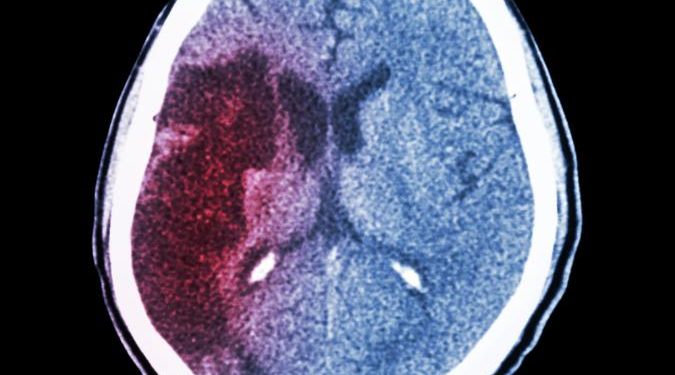

Bleeding in the brain (intracerebral hemorrhage) disrupts blood flow, making it harder for nearby brain tissue to get enough blood. It’s also dangerous because accumulated blood puts pressure on the brain and can damage it, especially if the brain is already damaged by other causes.

A CT scan is the best way to see if you or someone else has this kind of stroke. It can show where the bleed is located and how big it is. It can also help rule out other causes, such as a tumor or an infection.